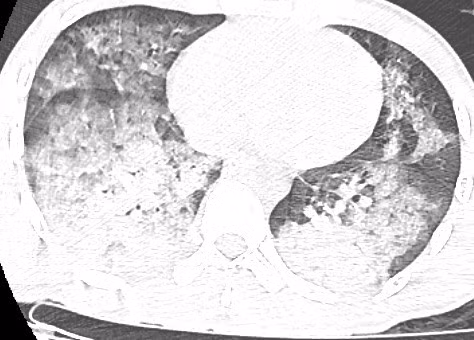

Hình ảnh kính mờ (ground-glass opacity) kèm đông đặc phế nang trên phim chụp CLVT của người bệnh Đ. - Ảnh BVCC